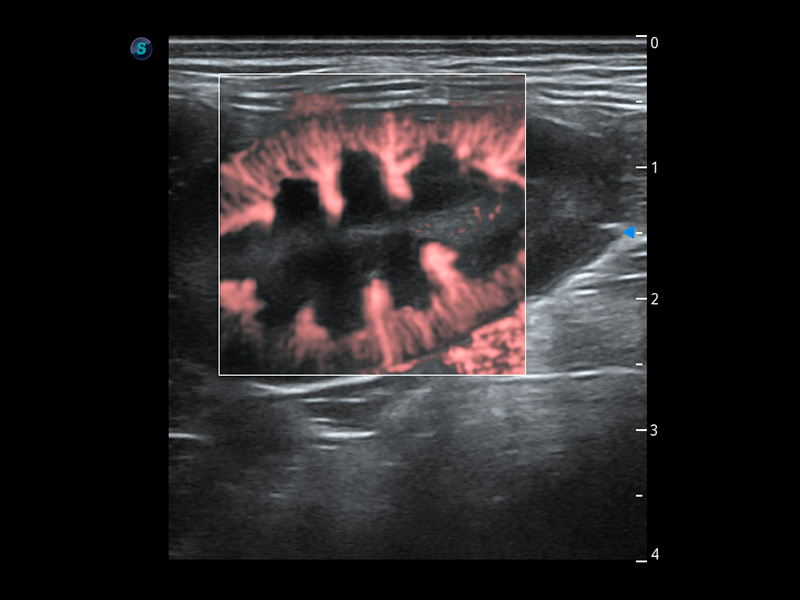

PDI 能量多普勒血流

提供高灵敏度和空间分辦率的血流图像,获得更加真实和丰富的诊断信息。